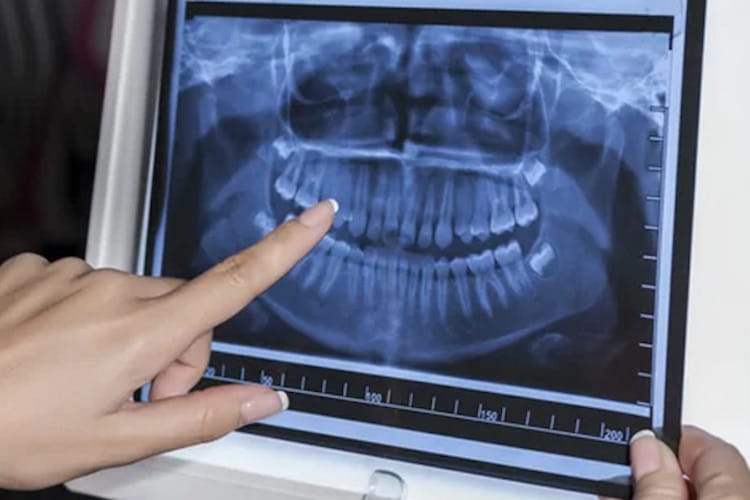

- Panoramic X-ray: This type of X-ray takes a wide-shot picture of your entire mouth! It captures all your teeth in both jaws, the jawbone, and even the sinuses. It’s helpful for getting a general overview of your mouth, checking wisdom teeth development, and planning orthodontic treatment (braces).

The final X-ray image, whether on film or digital, appears in shades of gray. Denser areas, like your teeth and jawbone, show up lighter because they block more of the X-rays. Less dense areas, like your gums or air pockets, appear darker because they allow more X-rays to pass through. By analyzing these variations in gray, your dentist can identify problems. For instance, a cavity might appear dark because it doesn’t block X-rays well, and areas of bone loss might also appear darker due to less dense bone being present.